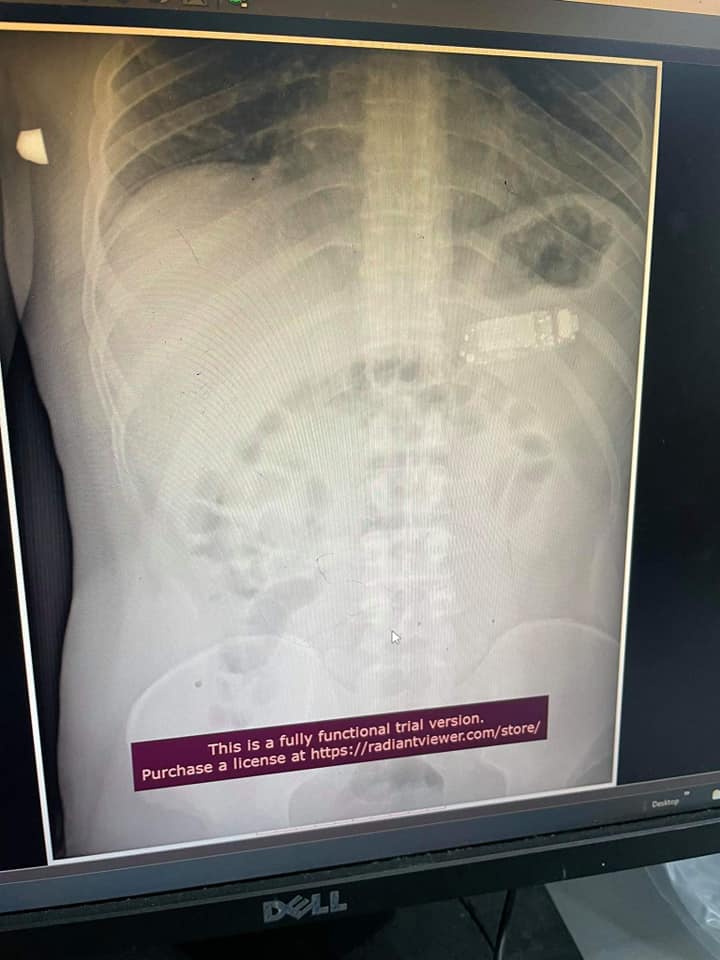

បើតាមក្រុមវេជ្ជបណ្ឌិតបានប្រាប់ឲ្យដឹងថា ជនរងគ្រោះបានកើតមានអាការៈចុកឆ្អល់ពោះយ៉ាងខ្លាំងមុនពេលទៅដល់មន្ទីរពេទ្យ ហើយភ្លាមៗនោះគេគិតថា គាត់ទំនងជាពុលអាហារ។ យ៉ាងណាក្តី នៅពេលស្ថានភាពជនរងគ្រោះកាន់តែអាក្រក់ឡើងៗ ខាងគ្រូពេទ្យបានសម្រេចថត X-Ray លើជនរងគ្រោះនិងបានរកឃើញមានទូរស័ព្ទមួយគ្រឿងនៅក្នុងពោះរបស់គាត់តែម្តង។ ក្រុមវេជ្ជបណ្ឌិតក៏បានបញ្ជាក់ផងដែរថា បើជនរងគ្រោះមកពេទ្យយឺតជាងនេះបន្តិចគឺគាត់អាចនឹងមានគ្រោះថ្នាក់ដល់ជីវិត ព្រោះនៅពេលដែលថ្មទូរស័ព្ទផ្ទុះគឺវានឹងបង្កើតឲ្យមានសារធាតុពុលយ៉ាងច្រើនជ្រាបចូលទៅក្នុងរាងកាយរបស់គាត់៕